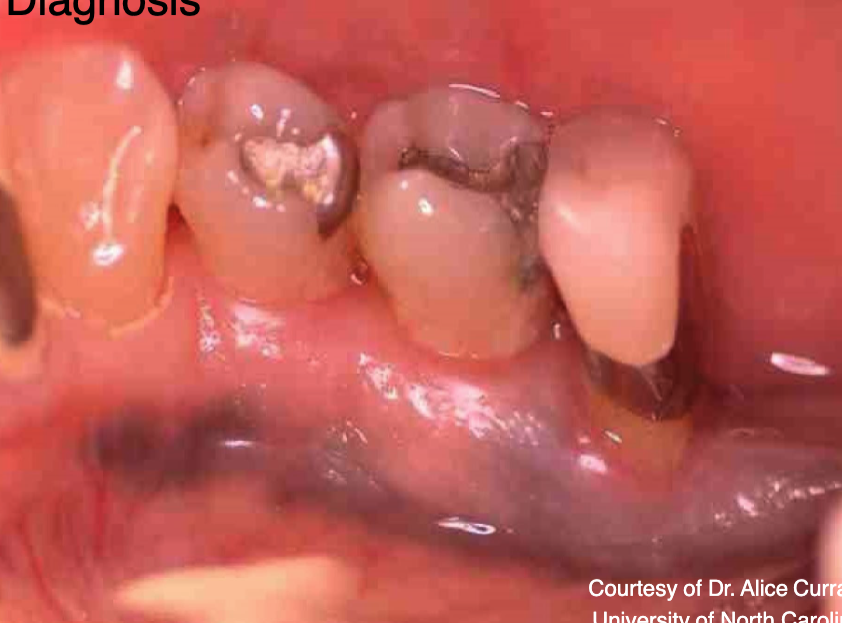

what is this

graphite tattoo